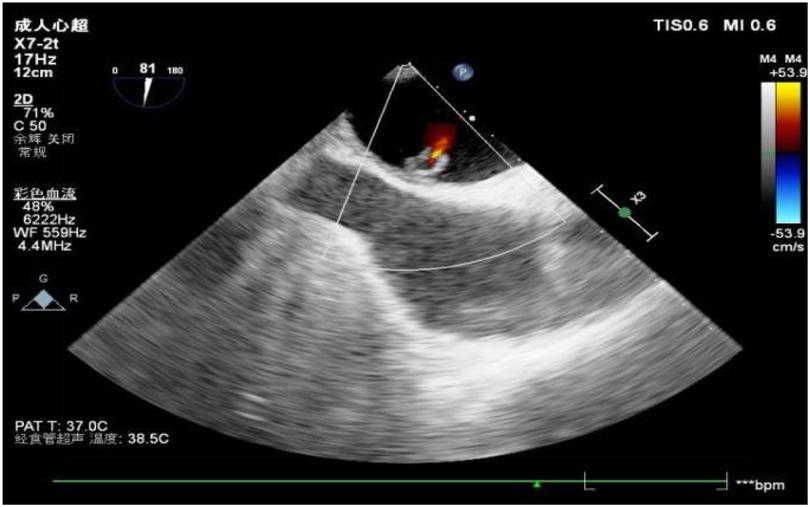

Figure 3

www.frontiersin.org

Figure 3. Color Doppler images showed intra-tumoral blood flow and blood stream draining from the mass.

A 56-year-old man with a 5-year history of paroxysmal palpitations, which have worsened over the past year, was diagnosed with atrial fibrillation. His vital signs and test results were within the normal range at that time. During evaluation, two- (2D) and three-dimensional (3D) transesophageal echocardiography (TEE) revealed a 17.8 mm × 11 mm LA tumoral mass, attached to the atrial septal fossa ovale (Figure 1). Multiplane TEE identified the mass as a tumor with heterogeneous echogenicity, suggesting myxoma (Figure 2). Color Doppler images showed intra-tumoral blood flow and blood stream draining from the mass (Figure 3). Left atrium computed tomography angiography (CTA) showed no signs of thrombosis but did reveal a mass in the left atrium arising from the atrial septal (Figure 4). Coronary CTA suggested intra-tumoral neovascularization with vascular channels supplied by a branch of the LCX (Figure 5). Coronary angiography (CAG) revealed a coro-cameral fistulous connection between a branch of the LCX and the LA. Furthermore, it showed the feeding arteries of the mass arising from the LCX (Figure 6). The rest of the CAG was normal. The patient was scheduled for surgical resection of the LA mass and repair of the coronary fistula. Pre-cardiopulmonary bypass (CPB) TEE demonstrated a bloodstream spurting from the tumor with a peak velocity of 70 mm/s. Intraoperative exploration revealed a 1.7 cm × 1.0 cm jelly-like, brittle LA mass attached to the atrial septal fossa ovale (Figure 7). An abnormal coronary artery of the coronary artery fistula was located within the atrial septal muscle bundle and was approximately 1.0–1.5 mm in diameter (Figure 8). The intraoperative probe confirmed that the rupture of the feeding artery or its branches resulted in a coronary artery–left atrial fistula. The abnormal opening of the feeding artery was located at the upper end of the atrial septal incision (Figure 9). The LA mass was successfully resected via the right atrial approach using a standard hypothermic CPB. Surgical ligation was executed to ensure complete sealing of the supplying coronary branch within the atrial septum. The patient was transitioned from CPB with the support of a minimal dose of dopamine. Post-procedure TEE confirmed complete resection of the LA mass and no flow across the atrial septal. The postoperative course was uneventful, and transthoracic echocardiography (TTE) showed no abnormal flow in LA. Histopathological analysis confirmed the diagnosis of myxoma accompanied by calcification and hemosiderin accumulation, revealing a multinucleated giant cell response, extensive cardiac cell degeneration, and localized infiltration of chronic inflammatory cells into the interstitium (Figure 10). The 6-month follow-up showed no recurrence of myxoma and recovery of sinus rhythm after radiofrequency ablation.